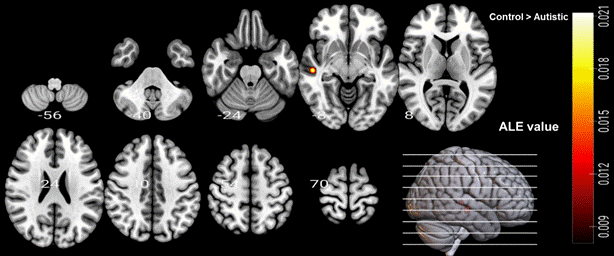

组内分析表明,在听觉语言理解任务中,两组被试的双侧颞上回(bilateral STG)都被激活,非孤独症组被试的左侧额上回(left SFG)和背内侧前额叶皮层(dmPFC)被激活(见图2)。此外,组间分析表明,与非孤独症对照组相比,孤独症组的右侧颞上回(right STG)、左侧颞中回(left MTG)和脑岛(insula)显示较低的激活,而孤独症组在任何区域相对于非孤独症组均未显示激活增加(见图3)。

图3. 组间分析ALE结果(孤独症组 vs. 非孤独症组)